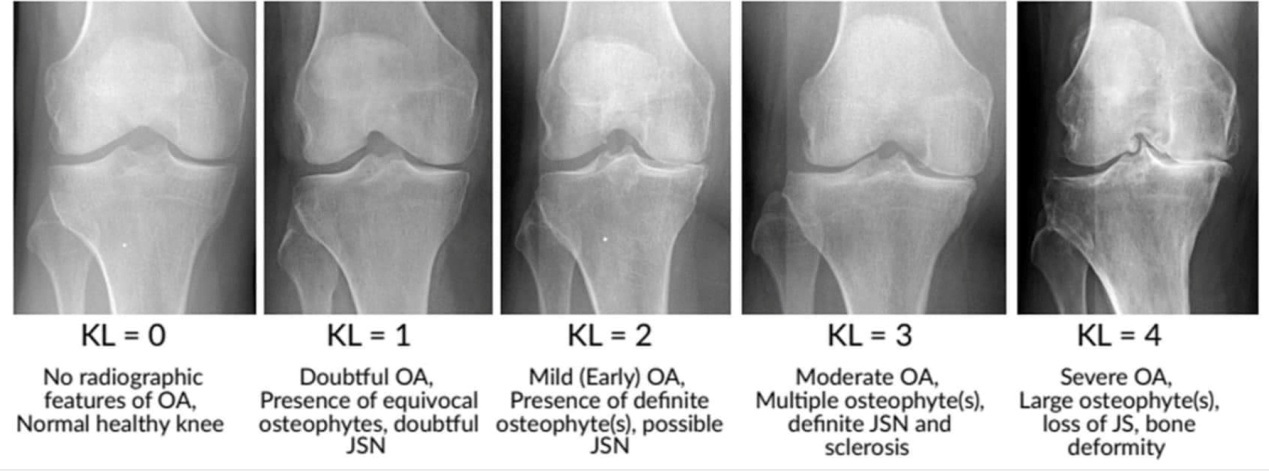

Η οστεοαρθρίτιδα είναι μια προοδευτική εκφυλιστική πάθηση που επηρεάζει τις αρθρώσεις σε άτομα ηλικίας 50 ετών και άνω. Η άρθρωση του γόνατος είναι αυτή που προσβάλλεται συχνότερα. Η οστεοαρθρίτιδα εμφανίζεται όταν μια άρθρωση υπόκειται σε καταπόνηση για παρατεταμένο χρονικό διάστημα. Η καταπόνηση οδηγεί σε φθορά του χόνδρου που βρίσκεται μεταξύ των δύο αρθρικών επιφανειών, γεγονός που αναγκάζει τις επιφάνειες αυτές να τρίβονται μεταξύ τους και να φθείρονται με την πάροδο του χρόνου. Η εκφυλιστική αυτή διαδικασία προκαλεί ερεθισμό και φλεγμονή της εσωτερικής επένδυσης της αρθρικής κάψας, η οποία εκδηλώνεται κλινικά με πόνο, οίδημα και δυσκαμψία. Η οστεοαρθρίτιδα του γόνατος είναι ένα πολύ συχνό πρόβλημα της τρίτης ηλικίας. Προκαλεί πόνο γύρω από την άρθρωση που αυξάνεται με την κίνηση και την άρση βάρους και βελτιώνεται με την ανάπαυση. Μπορεί να συνυπάρχει πρωινή δυσκαμψία και πρήξιμο στην άρθρωση. Το εύρος κίνησης της άρθρωσης είναι μειωμένο. Η ακτινογραφία είναι ενδεικτική του βαθμού εκφύλισης του χόνδρου ανάμεσα στις αρθρικές επιφάνειες.